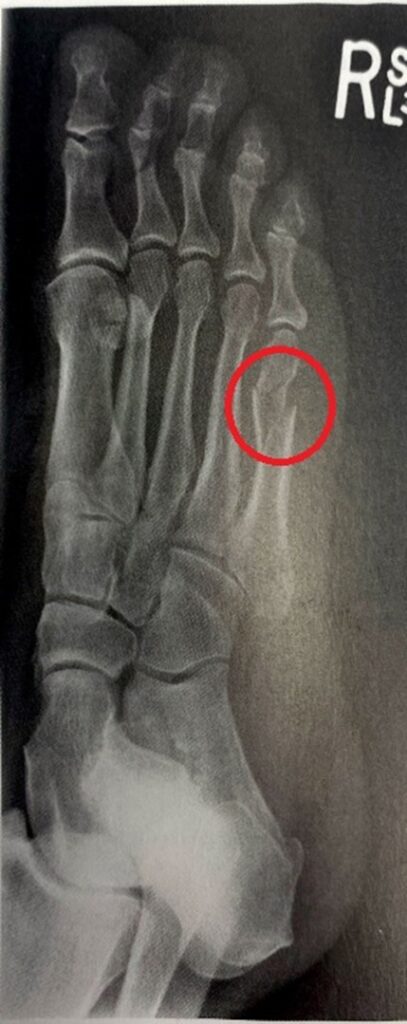

Złamanie 5 kości śródstopia zazwyczaj jest dobrze widoczne i potwierdzane zdjęciu RTG. W przypadku niejasnego obrazu dla potwierdzenia czasami wykonuje się badanie rezonansem magnetycznym. Złamania zmęczeniowe V kości śródstopia mogą być szczególnie trudne w jednoznacznej ocenie.

Podstawowym badaniem potwierdzającym złamanie V kości śródstopia jest RTG.

W przypadkach złamań zmęczeniowych zdarza się, że obraz RTG nie daje odpowiedzi czy kość jest złamana. W tym przypadku zaleca się wykonanie rezonansu magnetycznego stopy.